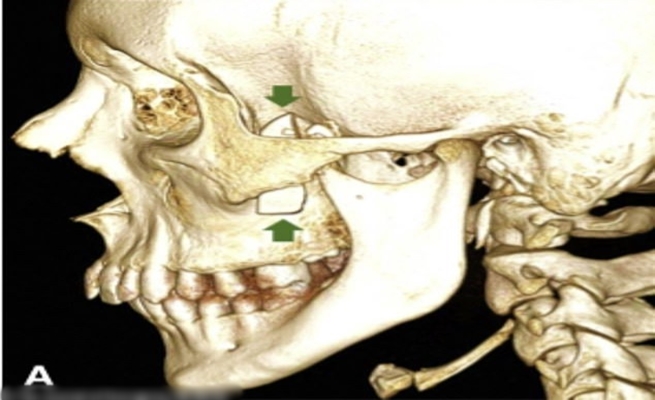

نجح الأطباء في إسبانيا بإزالة قطعة من الزجاج طولها 3.5 سم من داخل فك مراهق عمره 14 عامًا كانت سكنت وجهه بعد سقوط قطع زجاج إحدى النوافذ.

وأوضح الصبي أنه عولج منذ شهر بعدما جرح وجهه وسقط زجاج النافذة عليه، لكن بعد إجراء الأشعة السينية عثر الأطباء على جسم مخفي في وجه الصبي المجهول خلف عظام خده ووجدوا أنها قطعة زجاج من الحادث الأخير الذي تعرض له.

وبحسب صحيفة “القدس العربي”، وجد الأطباء زجاجة كانت على شكل شفرة سكين مخبأة في الجانب الأيسر من وجه الصبي، معربين عن حيرتهم الشديدة وخاصة أن الاختراق كان غير عادي لأن تلك المنطقة من الوجه محمية بشكل جيد.